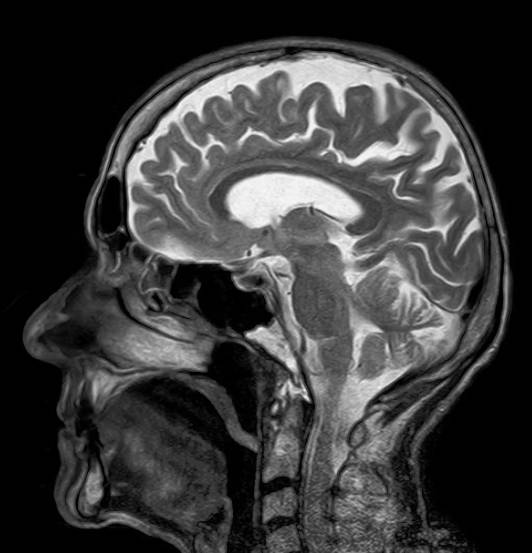

MRI는 Magnetic Resonance Imaging(자기 공명영상)의 약자로, 말 그대로 인체 내부를 고화질 영상으로 보여주는 비침습적 검사입니다.

뇌, 척추, 관절, 복부 장기 등 연부조직(근육, 신경, 디스크 등)의 이상 여부를 정밀하게 확인할 수 있어, 주로 종양, 염증, 뇌경색 흔적, 디스크 등을 진단할 때 사용됩니다.